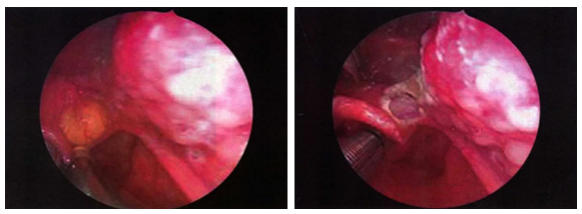

图为咽喉内镜下会厌囊肿切除术